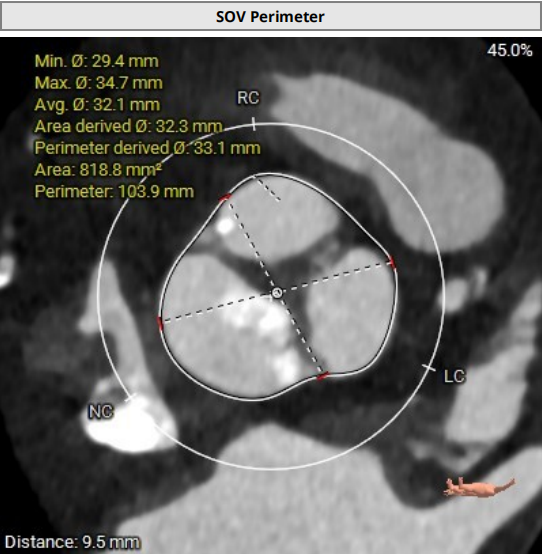

根部结构:Type1二叶瓣(L-R型),左右之间纤维钙化融合嵴,轻中度钙化伴瓣叶增厚,瓣环:22.0mm,左室流出道 :22.1mm,瓦氏窦:33.1mm,瓣上限制区(supra-8mm):21.5mm,极小心腔。

SOV:33.1mm(高:9.5mm)

STJ:30.9mm(高:23mm)